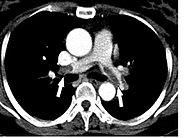

In the JNM study, titled “Detection of Pulmonary Embolism with Combined Ventilation—Perfusion SPECT and Low-Dose CT: Head-to-Head Comparison with Multidetector CT Angiography,” researchers in Denmark tested the diagnostic accuracy of SPECT/CT imaging for pulmonary embolism against that of multidetector CT angiography (MDCT) alone, which is the current first-line imaging technique for diagnosing pulmonary embolism. Their study found that SPECT plus low-dose CT had a sensitivity of 97 percent and a specificity of 100 percent, whereas MDCT alone had a sensitivity of 68 percent and a specificity of 100 percent. Having an effective technique for diagnosing pulmonary embolism leads to more rapid and successful diagnosis.

In a related article also published in this month’s JNM, researchers discuss the role of SPECT in imaging pulmonary embolism and how the technology has advanced. The authors of “SPECT in Acute Pulmonary Embolism” write that there is renewed interest in this modality as the initial imaging test for pulmonary embolism as a result of improved instrumentation and improved interpretation of lung scans, as well as concerns about high radiation exposure from CT angiography, particularly to the female breast. The article supports the conclusions found by the researchers in Denmark—SPECT/CT imaging may considerably improve the diagnosis of pulmonary embolism. The article also suggests that SPECT might be useful for follow-up examinations for determining therapy’s response.